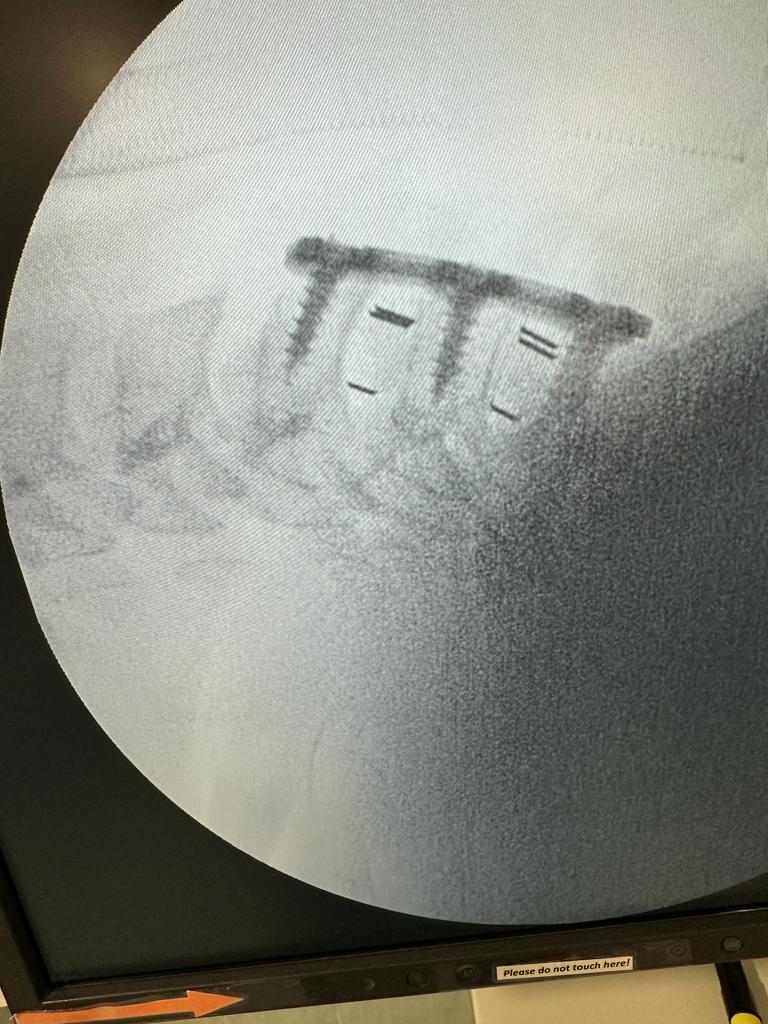

The work we do

S.T.D Neurosurgical Health Centre